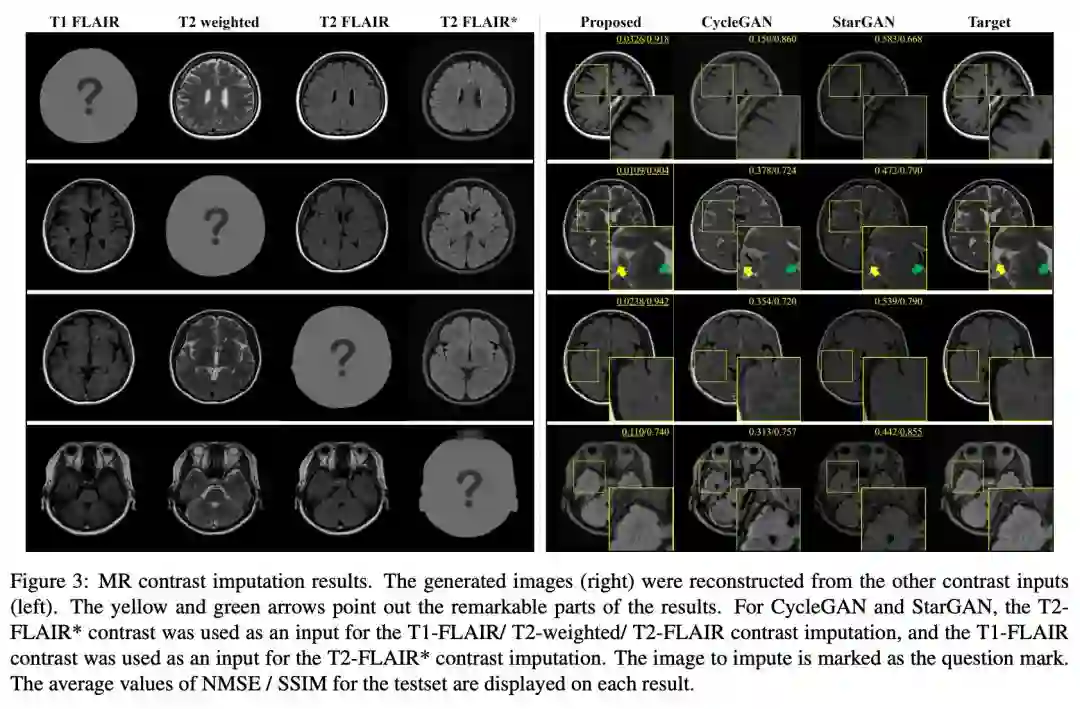

文章主要在三个数据集下进行实验测试,MR contrast synthesis 数据集是通过多动态多回波序列和来自 10 个受试者的附加 T2 FLAIR(流体衰减反转恢复)序列扫描总共 280 个轴脑图像。

在数据集中有四种类型的 MR 对比图像:T1-FLAIR (T1F),T2-weighted(T2w),T2-FLAIR (T2F) 和 T2-FLAIR (T2F)。前三个对比度是从磁共振图像编译(MAGiC,GE Healthcare)获得的,T2-FLAIR * 是通过第三对比度(T2F)的不同MR扫描参数的附加扫描获得的。MR contrast synthesis 数据集也是作者进行本次研究的目的性数据集。

在 MR 的数据集上,实验对比了 CycleGAN、StarGAN 和 CollaGAN:

从医学分析上 T2-weighted 图像中的脑脊液(CSF)应该是明亮的,上图中的第二行结果,这个在 CollaGAN 上效果最佳,在 StarGAN 和 CycleGAN 上则是暗淡的,在另外两个数据集下的定性测试上,CollaGAN 也展示优势:

在定量分析上,作者采用重建和目标之间计算归一化均方误差(NMSE)和结构相似性指数(SSIM)来衡量,文章还花了一定篇幅介绍了 SSIM 的度量计算公式(感兴趣的可以自行阅读原文)。在定量上对比 CycleGAN 和 StarGAN 得到了优异的效果。